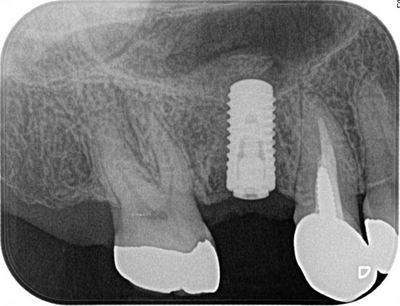

右上第一大臼歯中間欠損へのインプラントオペを行います。

CTでシミュレーションをします。インプラント治療にはもはやCTは必須です。

骨の垂直幅は8mm弱ですがソケットリフトを行い10mmのインプラントを

植立する予定を立てます。